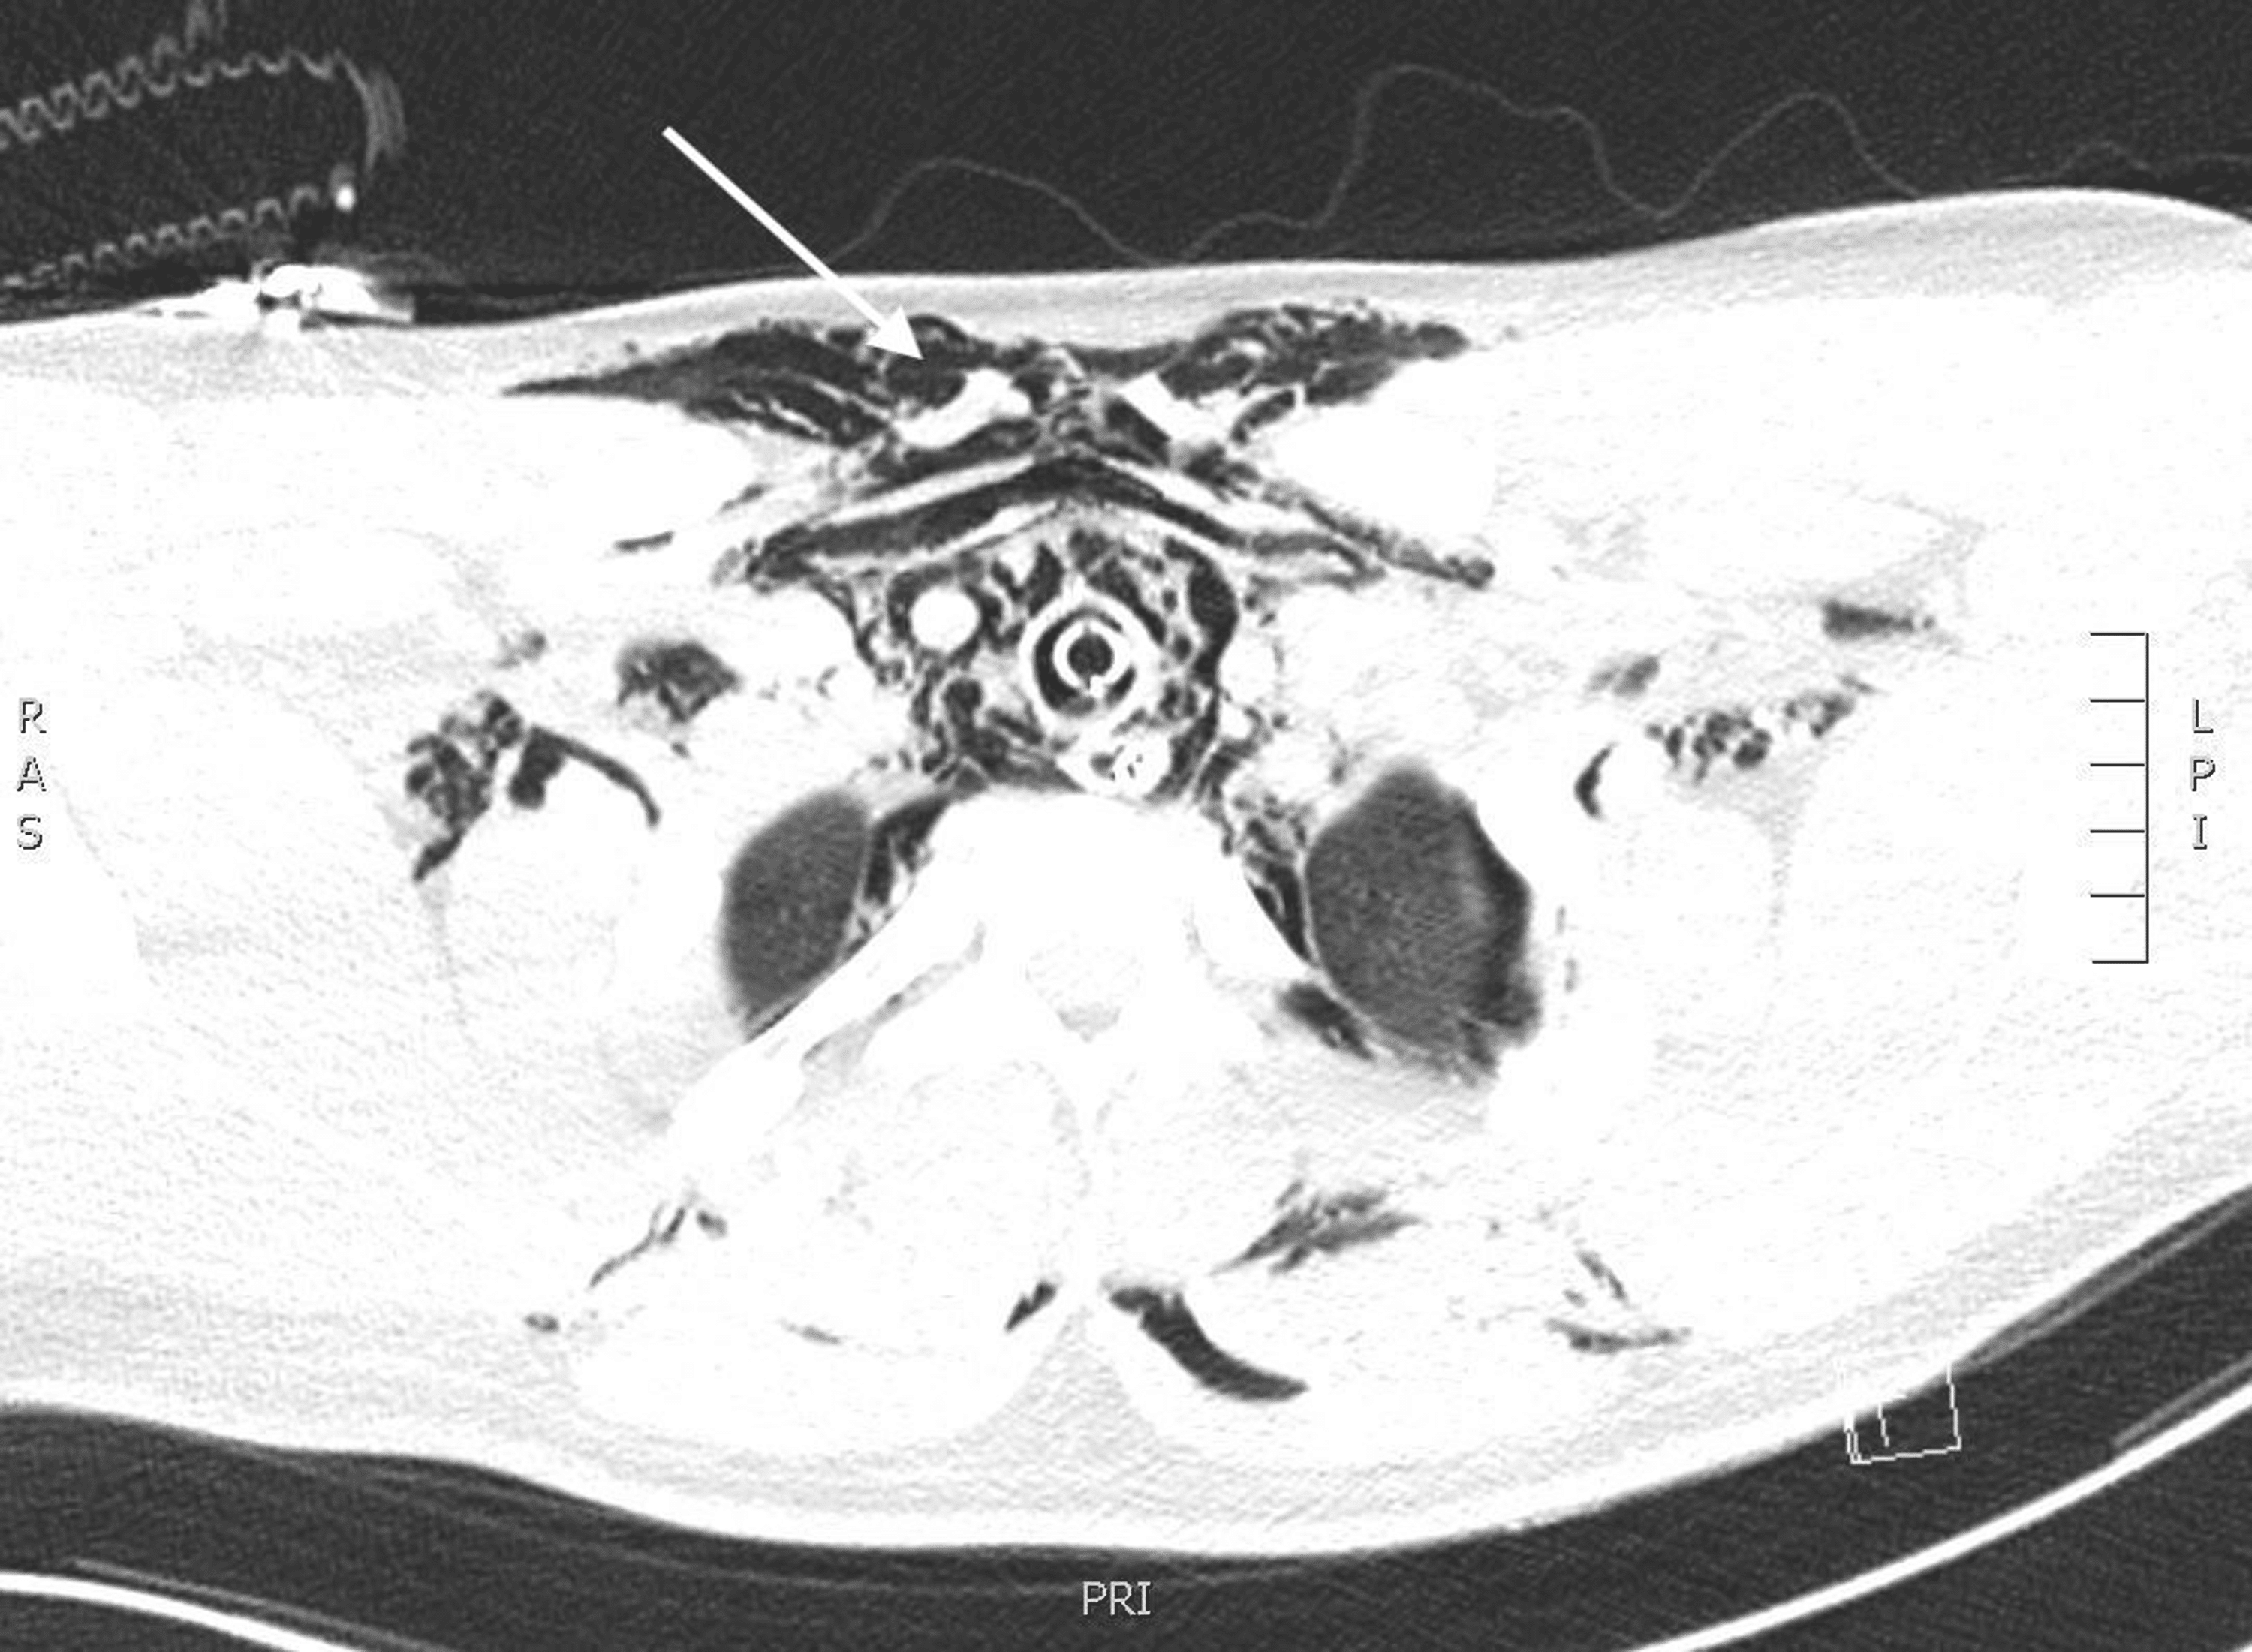

Pathophysiology of divingrelated pulmonary barotraumas. A variety of

Pathophysiology of divingrelated pulmonary barotraumas. A variety of Lung Barotrauma Diving Patients at high risk for. He presented with chest pain after. Proper ascent timing and techniques are essential. To prevent pulmonary barotrauma, people must freely exhale any air inhaled at depth—even the depth of a swimming pool—during ascent. Rapid changes in lung air volume during descent or ascent can result in a lung injury known as pulmonary barotrauma. Prevention of. Lung Barotrauma Diving.